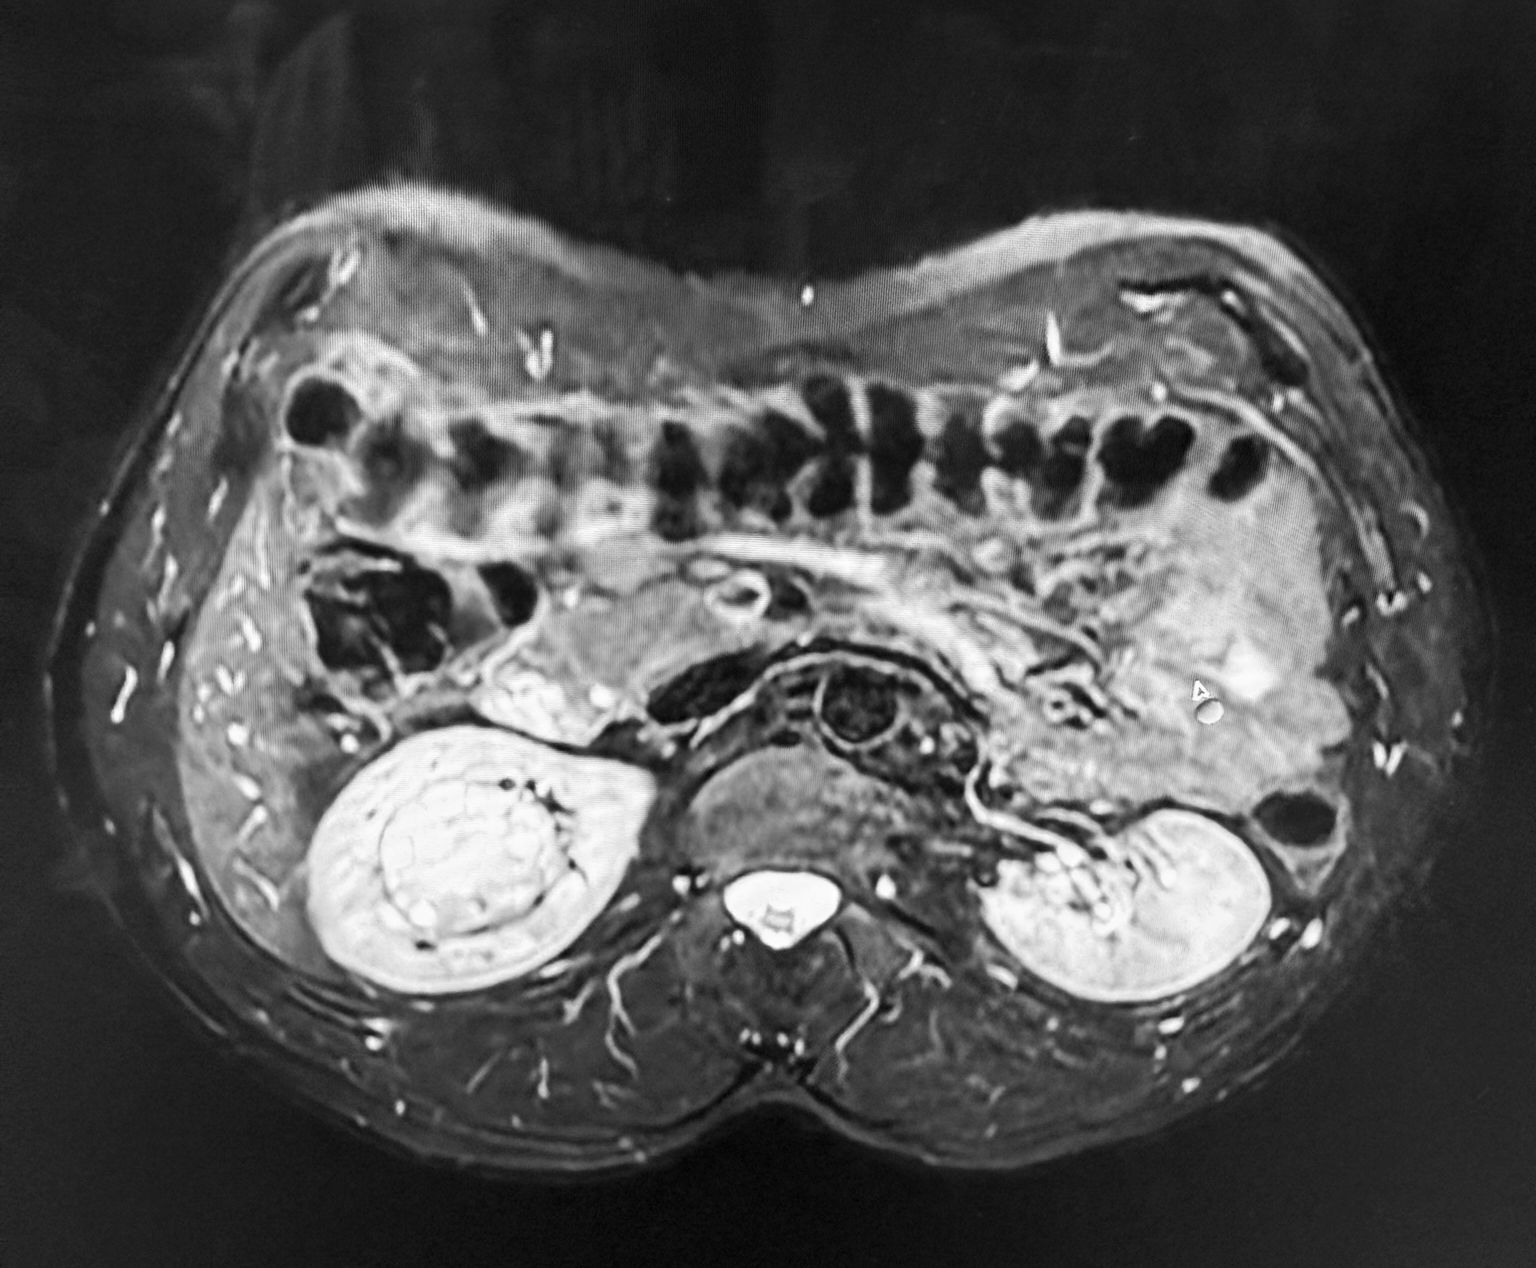

Większość nowotworów nerek rośnie w sposób egzofityczny, czyli wystaje poza obrys narządu, co znacznie ułatwia ich operacyjne usunięcie. W przypadku 44-letniego pacjenta było inaczej. Lekarze zdiagnozowali u chorego guz endofityczny. Nowotwór znajdował się w samym centrum nerki.

- To była wyjątkowa operacja. Zwykle zmiany mają dwa lub trzy centymetry i są położone na brzegu nerki, dlatego ich usunięcie nie sprawia większych trudności. W przypadku 44-letniego pacjenta guz osiągnął wielkość piłki tenisowej i był ukryty w miąższu narządu. Sytuację komplikował fakt, że leżał w bezpośrednim sąsiedztwie naczyń nerkowych. Aby go usunąć, trzeba było naciąć nerkę, wypreparować zmianę i zamknąć ubytek. Była to procedura bardzo trudna technicznie i obarczona ryzykiem. Zabieg był możliwy dzięki systemowi robotycznemu da Vinci. Umożliwia on operację w powiększeniu i obrazie 3D oraz pozwala precyzyjnie zszyć głęboki ubytek po guzie. Wykonanie zabiegu bez użycia tej technologii byłoby bardzo trudne, wiązałoby się z ogromnym ryzykiem uszkodzenia naczyń i koniecznością usunięcia całej nerki - mówi dr n. med. Przemysław Mitura, pełniący obowiązki Lekarza Kierującego Klinicznym Oddziałem Urologii i Onkologii Urologicznej Uniwersyteckiego Szpitala Klinicznego Nr 4 w Lublinie.